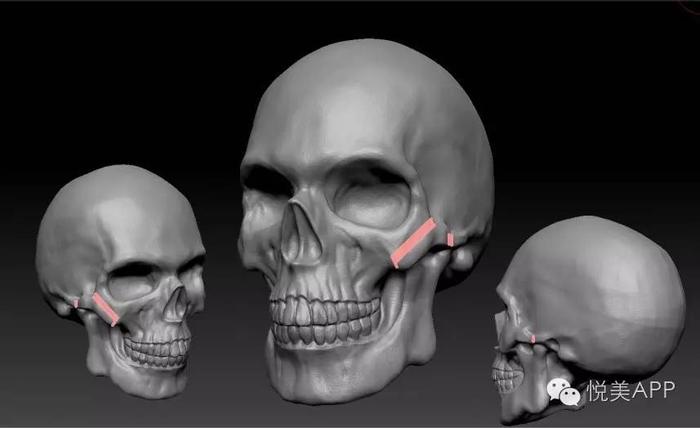

颧骨颧弓内推的极限是多少?

颧骨内推是有一定限度的,颧弓内推的极限决定于颧弓和下颌骨喙突之间的距离,颧弓内推只要不妨碍下颌骨喙突的运动,可以达到极限值。

下颌骨喙突位置:

也就是白色圆圈内的两块骨头距离,推太多会导致张口受限,影响功能